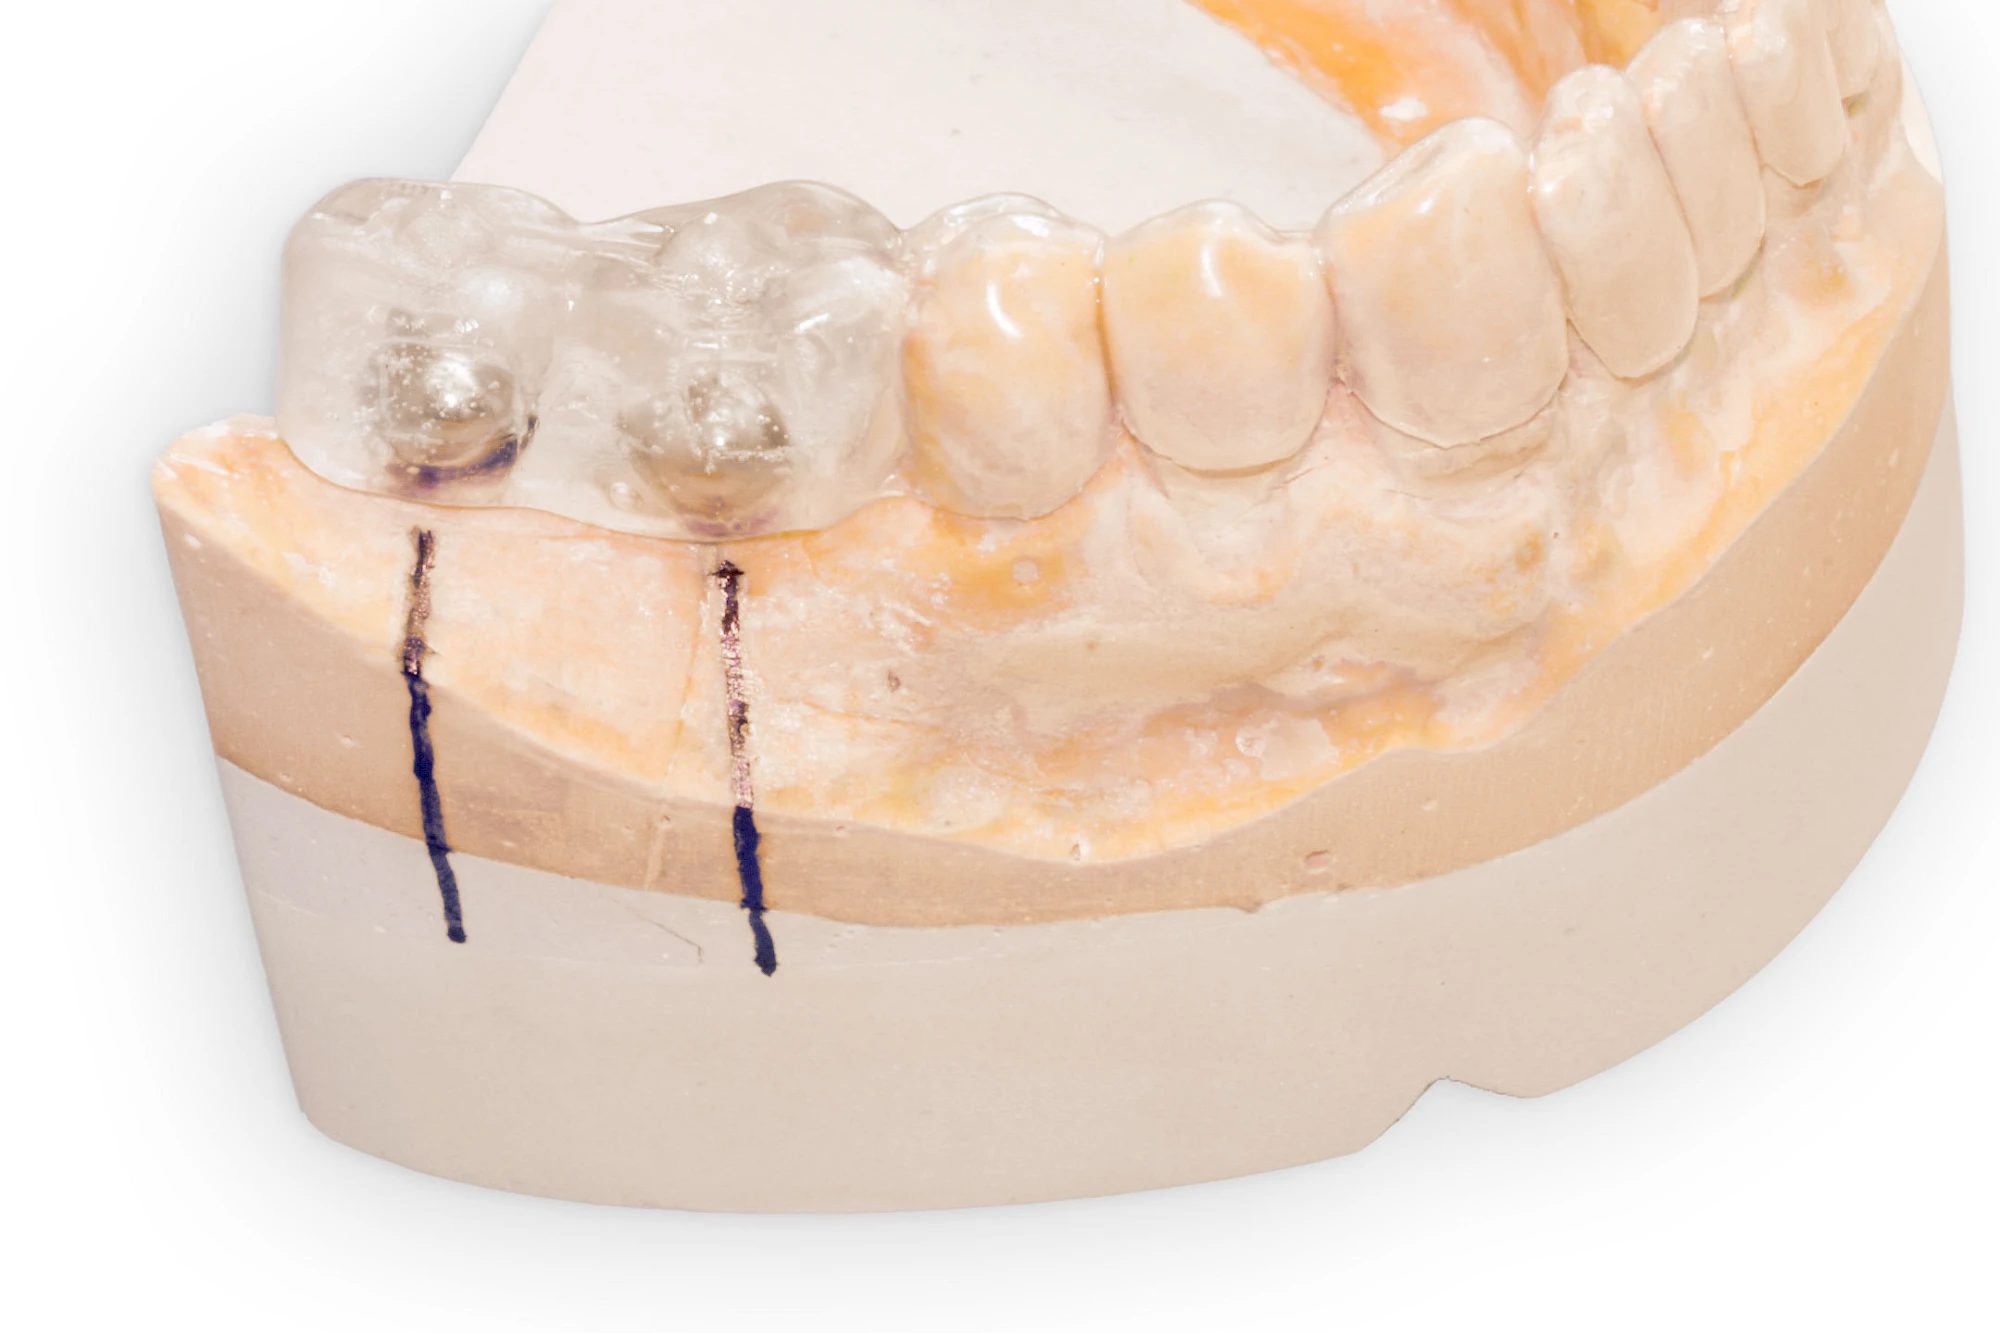

Implantatplanung

Damit Implantate an der richtigen Stelle im Kieferknochen platziert werden könen, gibt es heute vielfältige Möglichkeiten der Planung. In vielen Situationen kann die Erfahrung des Zahnarztes ausreichend sein.

Nicht selten ist jedoch auch eine technisch aufwändigere Vermessung im Vorfeld sinnvoll, z. B.:

- Wenn sich der Kieferknochen abgebaut hat

- Wenn der Nervverlauf im Unterkiefer beachtet werden muss

- Wenn die Ausdehung der Kieferhöhle im Oberkiefer beachtet werden muss

- Wenn wenige Restzähne keine gute Orientierung erlauben

In diesen Fällen kann die Planung mittels verschieden aufwendiger Röntgen-Techniken (Übersichtsaufnahme, DVT) ggf. unter Zuhilfenahme speziell angefertigter Planungsschablonen sinnvoll sein.